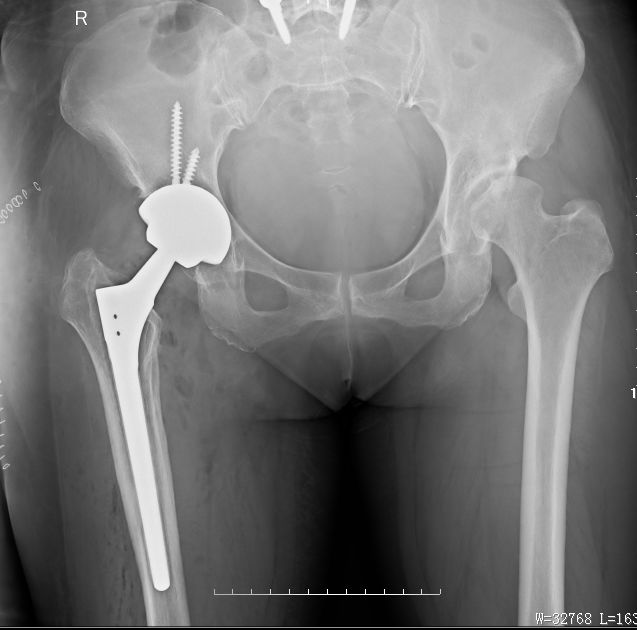

右髋翻修术后髋关节假体稳定,假体位置角度良好,可早期下地活动锻炼